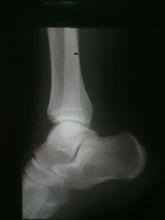

右距骨撕脫性骨折另外一種直白的解釋:韌帶(俗稱筋)跟肌肉和骨骼緊密相連,劇烈運動時韌帶極度收縮,導致韌帶控制相連的肌肉(再內層是肌腱)一塊極度收縮,收縮的幅度過大,同時骨骼突起和粗隆部分不夠結實,被肌腱的收縮力度一塊拉扯下來,從而造成撕脫性的骨折。

人在劇烈活動中可造成肌肉的收縮,與肌腱相連的骨的突起和粗隆部的一部分或者全部的骨質分離。由於韌帶牽拉造成韌帶附著處骨質隨韌帶一起剝離下來,形成碎骨片,稱為撕脫性骨折。(通俗點說就是肌肉肌腱拉力過大,在外力的作用下,導致附著的骨頭髮生骨折,撕裂下整塊或者一小部分的骨質殘片)

撕脫性骨折撕脫性骨折的症狀與骨折相近,以傷處疼痛及關節活動部分受限為主要表現,其次就是局部的腫脹,壓痛。脛骨髁間隆起撕脫性骨折是一種特殊類型的23關節內骨折,往往是前交叉韌帶或後交叉韌帶在脛骨附著部的撕脫性骨折。不適當的治療會導致畸形癒合,引起膝關節功能不穩。脛骨髁間隆起撕脫性骨折並移位多沿用傳統切開復位鋼絲內固定術治療。切開復位鋼絲內固定雖可有效的復位與固定骨折塊,但其有切口長,創傷大,術後功能鍛鍊極為痛苦和漫長,易發生膝關節僵直,加之髁間窩狹小操作不便等缺點。